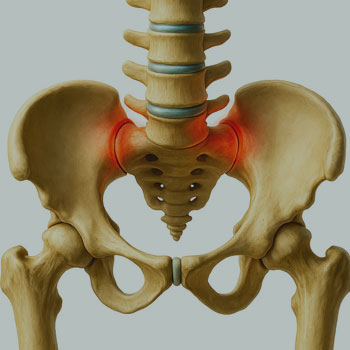

SACROILEÍTE